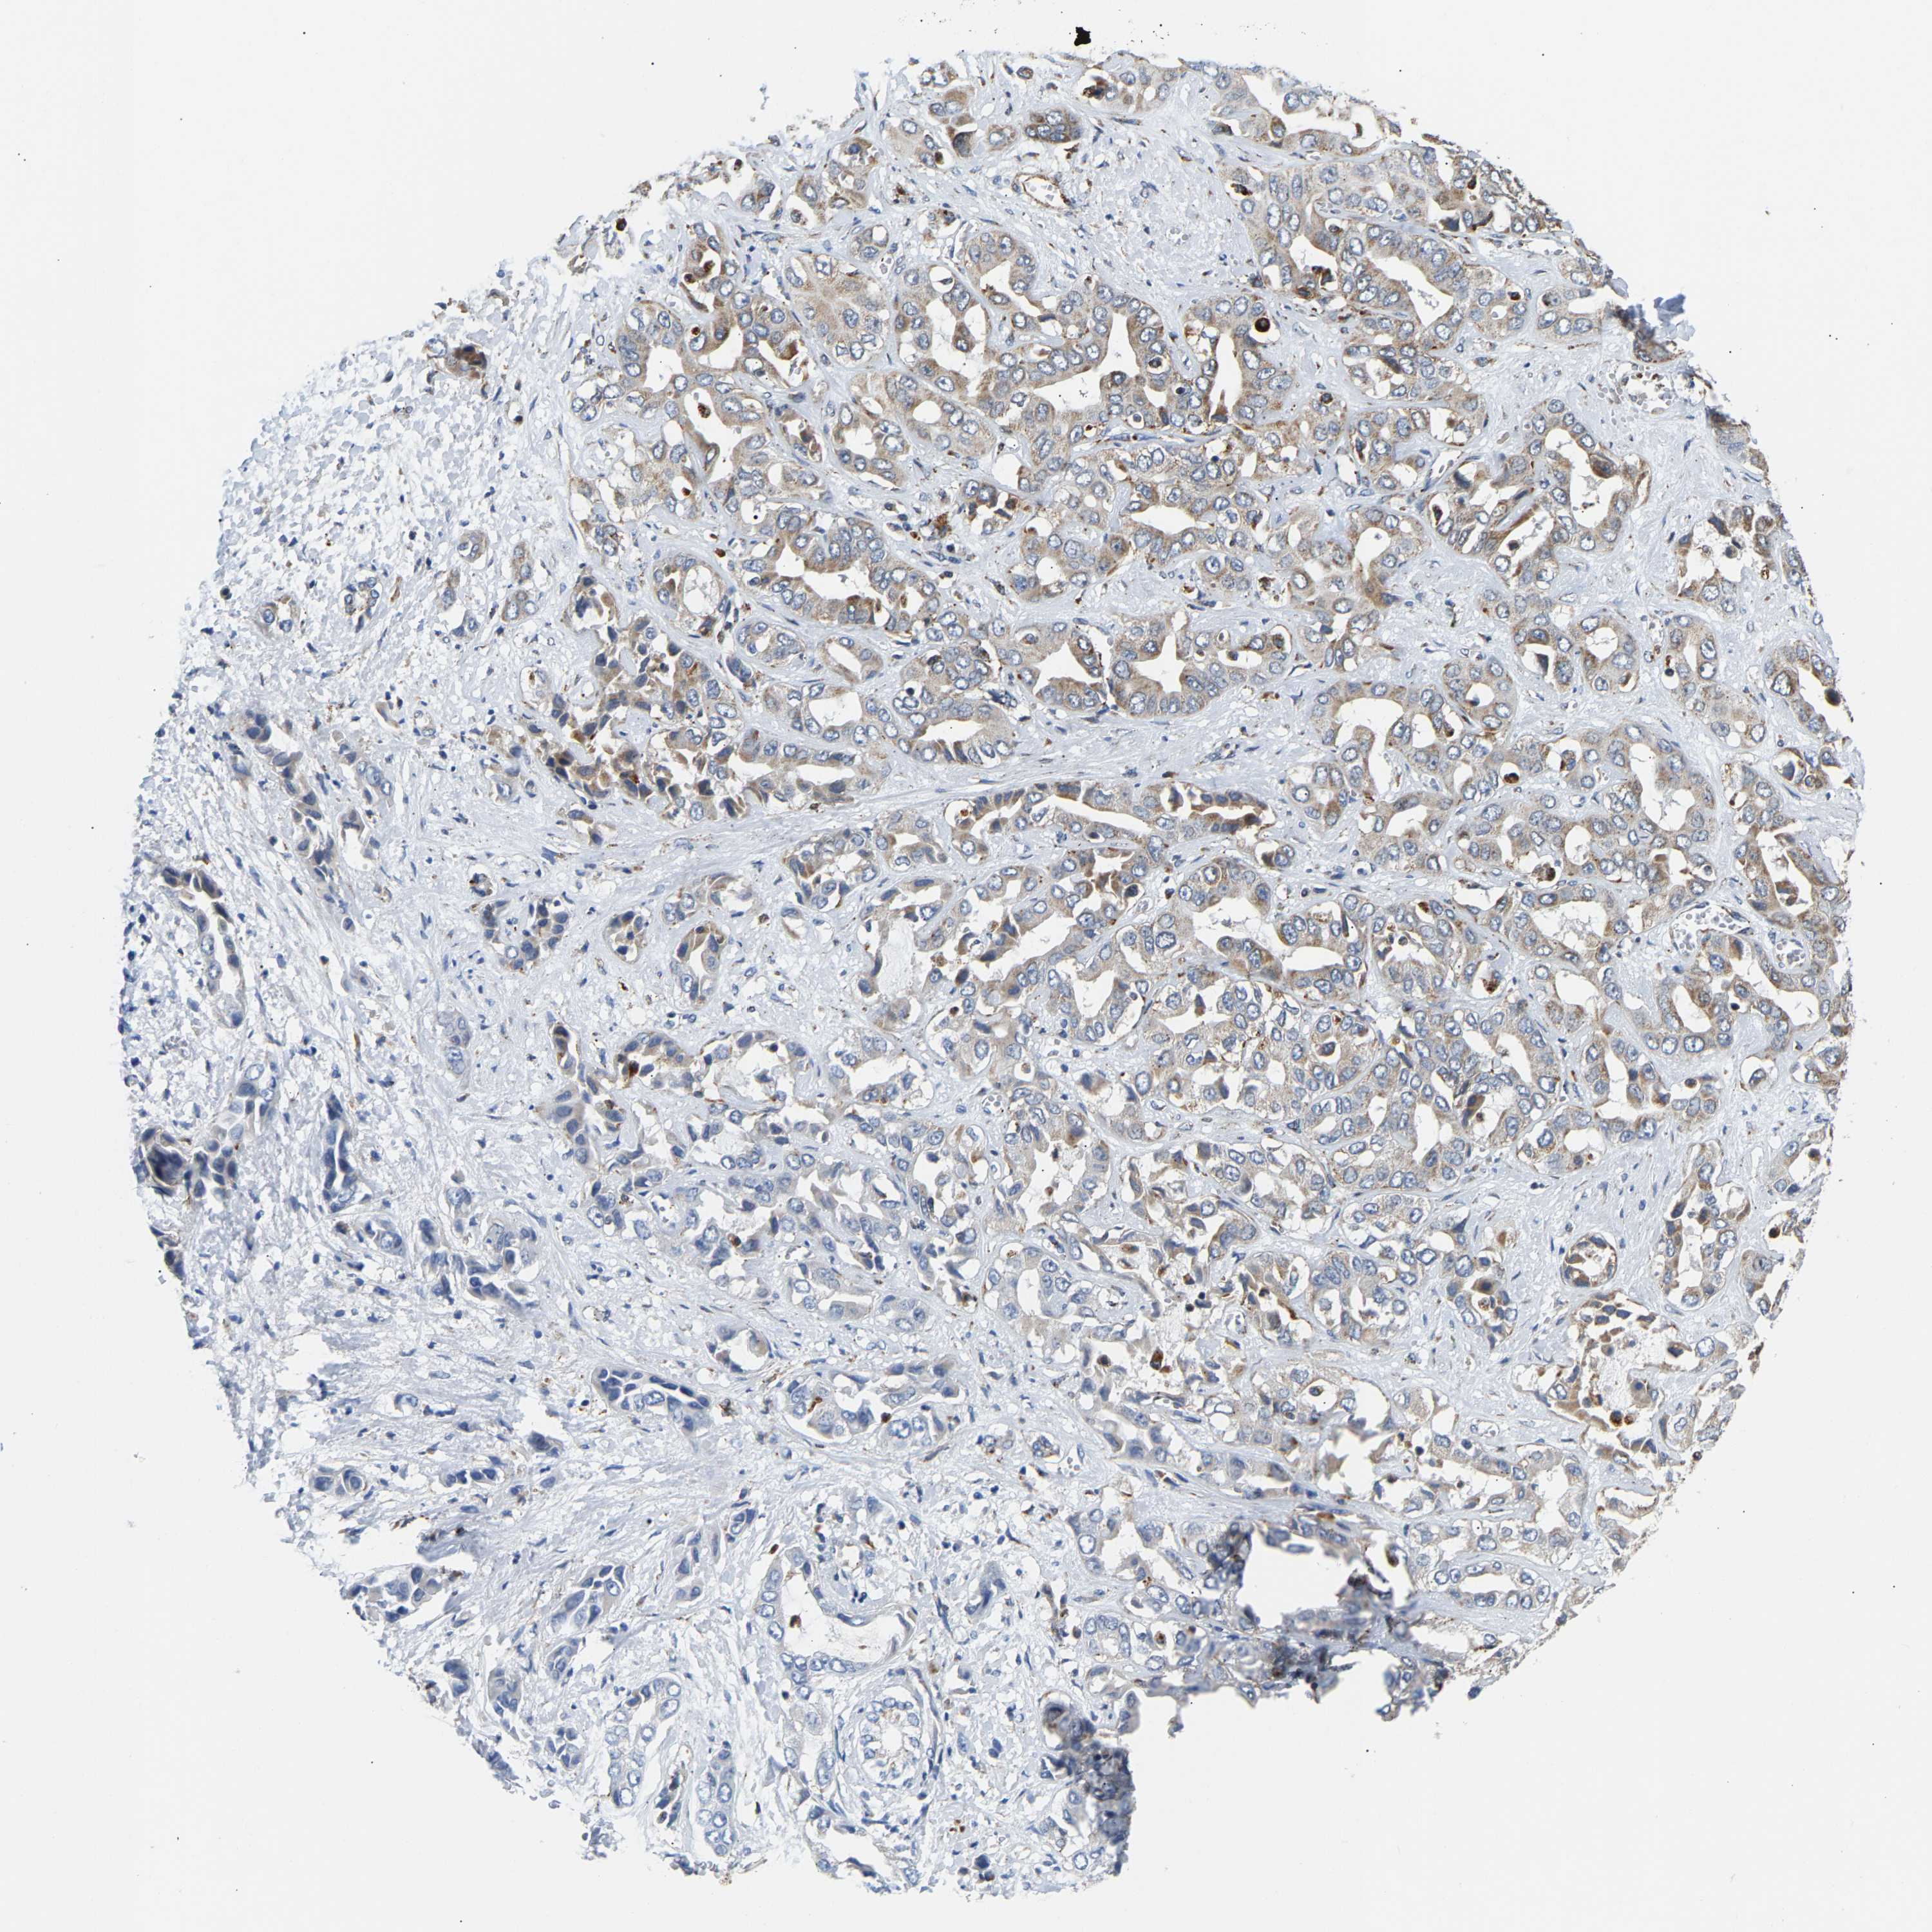

LIVER CANCER - Protein expressioni

A mouse-over function shows sample information and annotation data. Click on an image to view it in a full screen mode. Samples can be filtered based on level of antibody staining by selecting one or several of the following categories: high, medium, low and not detected. The assay and annotation is described here.

Note that samples used for immunohistochemistry by the Human Protein Atlas do not correspond to samples in the TCGA dataset.

Antibody stainingi

Antibody staining in the annotated cell types in the current human tissue is reported as not detected, low, medium, or high, based on conventional immunohistochemistry profiling in selected tissues. This score is based on the combination of the staining intensity and fraction of stained cells.

Each image is clickable and will lead to virtual microscopy that enables deeper exploration of all samples and also displays staining intensity scores, fraction scores and subcellular localization as well as patient and tissue information for each sample.

Antibody HPA020266

Antibody HPA020268

Staining

High

Medium

Low

Not detected

Intensity

Strong

Moderate

Weak

Negative

Quantity

>75%

75%-25%

<25%

None

Location

Nuclear

Cytoplasmic/membranous

Cytoplasmic/membranous,nuclear

Cholangiocarcinoma

Carcinoma, Hepatocellular, NOS